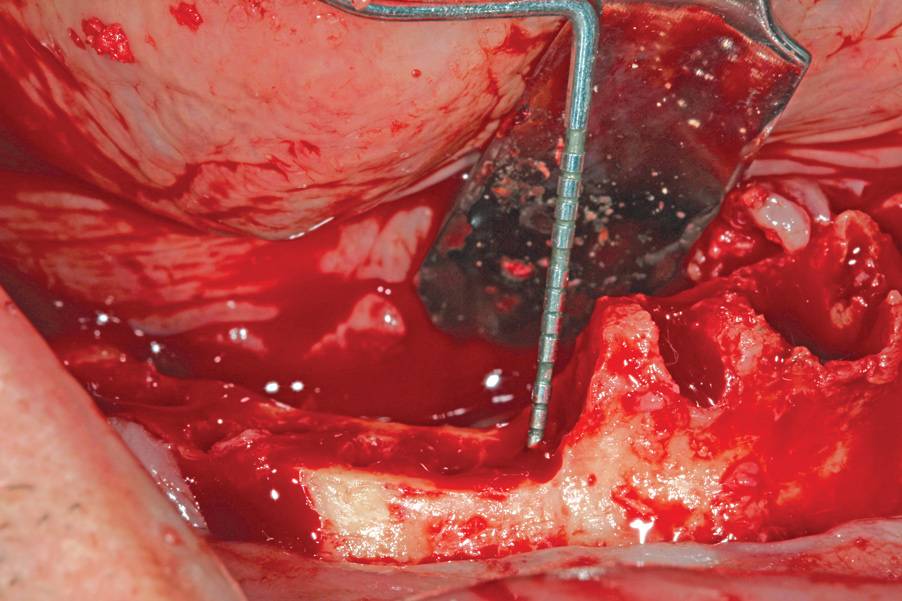

Fig 2. Sublingual arterial branch tied off with 4-0 chromic gut suture.

Figure 2

Following the administration of local anesthesia, the first step in All-on-4–style treatment is full-thickness mucogingival flap reflection. Depending on anatomic variability, vasculature such as the greater palatine artery or sublingual artery, or various branches thereof, may be disrupted. Should this occur, excessive hemorrhaging may obscure visibility of the surgical field in addition to becoming a hazard for the patient.

Initial treatment in these situations involves administration of local anesthetic with at least 1:100,000 epinephrine.21 In most cases, the vasoconstrictor effect of epinephrine is enough to stop the hemorrhaging. Should the vasoconstrictor fail to alleviate the problem, an electrosurgical generator or laser with a coagulation setting may be applied to the source of hemorrhage. A third option for containing the bleed is to use a resorbable suture to tie off the vessel posterior to the site of hemorrhage (Figure 2).